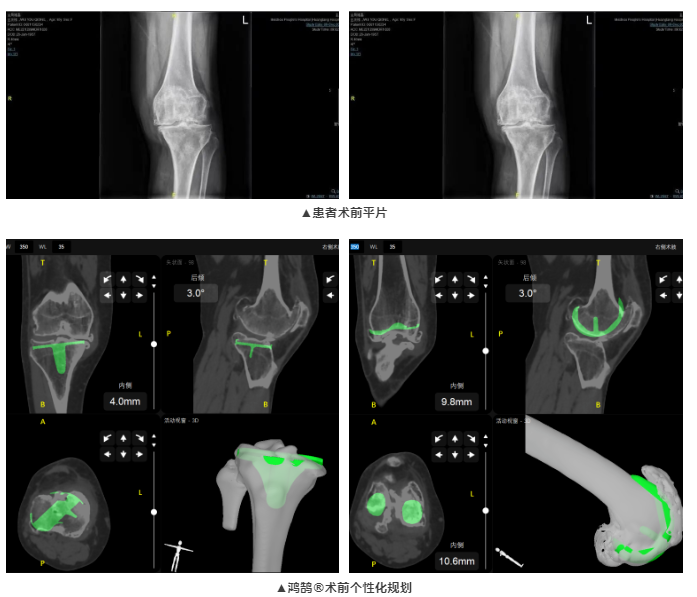

梅州市人民醫(yī)院成功完成首例鴻鵠?機(jī)器人輔助人工全膝關(guān)節(jié)置換手術(shù),鴻鵠?精準(zhǔn)、個(gè)性的術(shù)前3D規(guī)劃功能,協(xié)助醫(yī)生掌握更多患者信息,為患者制定個(gè)性化假體植入手術(shù)計(jì)劃

患者為65歲女性,雙膝疼痛20年,近日疼痛加劇,就診于梅州市人民醫(yī)院。術(shù)前經(jīng)檢查發(fā)現(xiàn)雙膝關(guān)節(jié)內(nèi)翻畸形,診斷為雙膝關(guān)節(jié)骨性關(guān)節(jié)炎。術(shù)前患者雙膝疼痛,導(dǎo)致行走功能受到明顯阻礙,嚴(yán)重影響生活質(zhì)量。廖紅興博士團(tuán)隊(duì)經(jīng)綜合評(píng)估,決定行鴻鵠?骨科手術(shù)機(jī)器人輔助全膝關(guān)節(jié)置換術(shù)。

本次全膝關(guān)節(jié)置換術(shù),術(shù)前,廖紅興博士團(tuán)隊(duì)通過(guò)鴻鵠?為患者進(jìn)行膝關(guān)節(jié)CT圖像三維重建,制定符合患者生理特征的個(gè)性化假體安裝方案,提高后續(xù)手術(shù)治療效率;術(shù)中,鴻鵠?引導(dǎo)完成機(jī)械臂注冊(cè)和骨注冊(cè),機(jī)械臂精準(zhǔn)定位到預(yù)期規(guī)劃位置,一體化截骨工具輔助醫(yī)生完成股骨脛骨截骨,進(jìn)而實(shí)現(xiàn)假體精確安放。